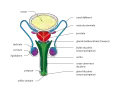

L'appareil génital masculin est l'appareil reproducteur de l'homme. Il est composé des cordons spermatiques, du scrotum, des testicules, des épididymes, des canaux déférents, des canaux éjaculateurs, des vésicules séminales, de la prostate, de l'urètre et du pénis.

Anatomie vue de côté Anatomie vue de face

Anatomie vue de face